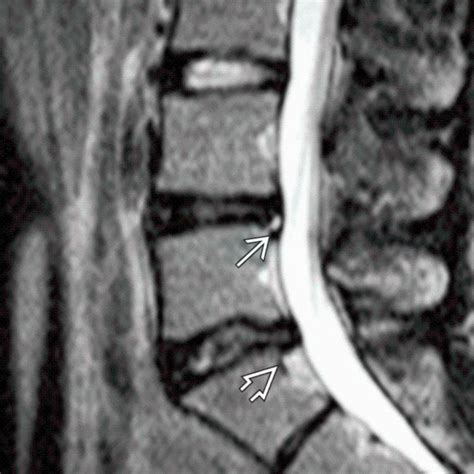

Therefore, if you are diagnosed with an OSC disc degenerative disc disease , it means that the diagnosis and potentially your treatment are being managed through an Orthopedic Spine Center or a similarly named facility. The specialists there will assess the condition of your spinal discs using various imaging techniques, such as X-rays, MRIs, or CT scans. These scans help them visualize the extent of the degeneration, identify any nerve compression, and rule out other potential causes of your symptoms. They’ll then tailor a treatment plan to address your specific needs, which might include physical therapy, pain medication, injections, or, in more severe cases, surgery.

So, when you see “Lwk” associated with degenerative disc disease , it means that the disc degeneration is occurring in the lumbar spine. This is a very common location for DDD because of the high stresses placed on the lower back. Symptoms of lumbar disc degeneration can include lower back pain, stiffness, and muscle spasms. The pain may radiate into the buttocks, hips, or even down the legs if there is nerve compression. This is often referred to as sciatica. The symptoms can vary depending on the severity of the degeneration and the specific discs involved. For example, degeneration of the L4-L5 disc may cause pain that radiates down the outer side of the leg and into the foot.